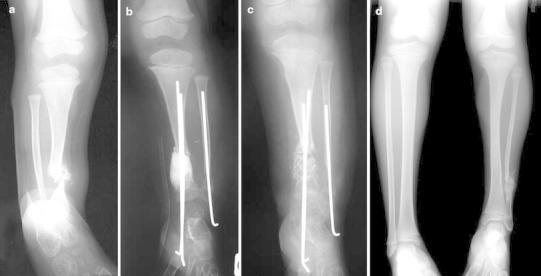

Fig. 1.

Case 1. a Anteroposterior radiograph showing congenital pseudarthrosis of the tibia (CPT) of the distal third of the tibia in a 30-month-old girl. b Postoperative radiograph of the first stage of the induced membrane technique with cement spacer on the tibia and osteosynthesis with two transplantar tibial K-wires and one fibular K-wire. c Postoperative radiograph of the second stage of the induced membrane technique after grafting in the biological chamber surrounded by the membrane. d Full-length standing anteroposterior radiograph of the lower limbs at follow-up of 6 years showing a discrepancy of 4 cm on the CPT side